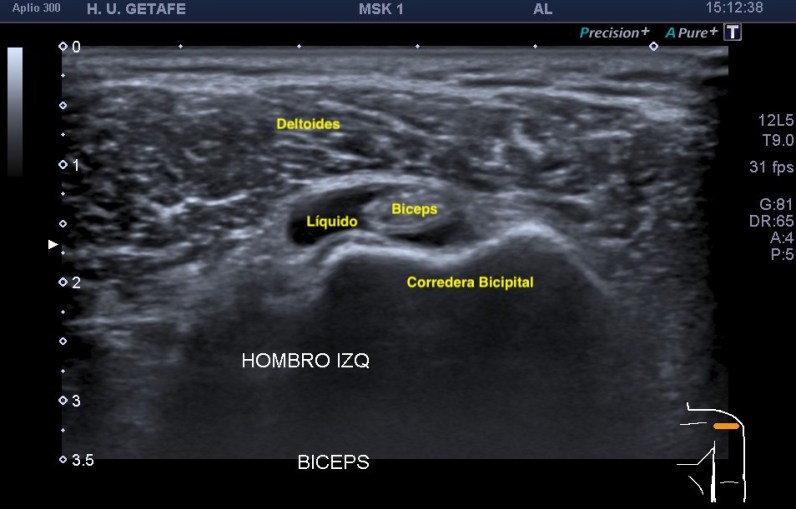

1.Tendón del biceps, cabeza larga.

Situada en la corredera bicipital, vas a ver el bíceps como una estructura hiperecogénica, redondeada situado en el valle de la corredera. Observa como la imagen superior indica ausencia de líquido y normalidad y la inferior relación entre la anatomía y la patología donde el líquido rodea el tendón en relación con una posible tenosinovitis.